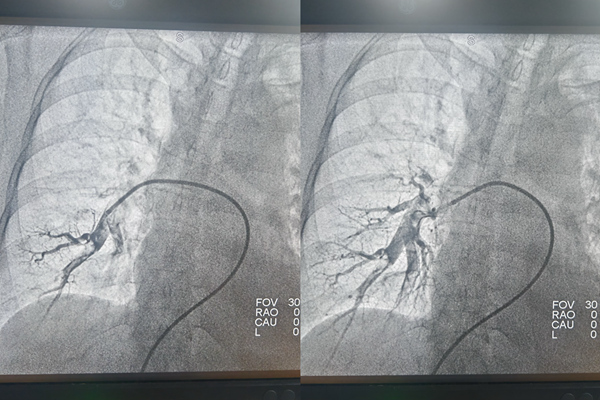

手術前后肺動脈造影對比。重慶兩江新區人民醫院供圖

孫曉龍通過患者雙側股靜脈穿刺,將一根如絲線般細的微導絲沿著血管送入雙側下肢靜脈進行造影。在X射線的實時監控下,治療團隊仿佛擁有“透視眼”,能清晰看到導絲的位置和血管血流情況,顯示左側骼靜脈重度狹窄,并內有血栓。沿著導絲再送入微導管進行造影,顯示左右兩側肺動脈內均有血栓。

隨后,通過導管抽吸出血栓,疏通“堵點”,肺動脈血流即刻恢復暢通。接下來解決左側骼靜脈重度狹窄問題。治療團隊向左側骼靜脈送入細導絲,并沿導絲送入一個小小的球囊,將狹窄的血管擴張開來,再于血管狹窄處放置一枚支架,支撐起狹窄的血管壁,使血流重新通暢。